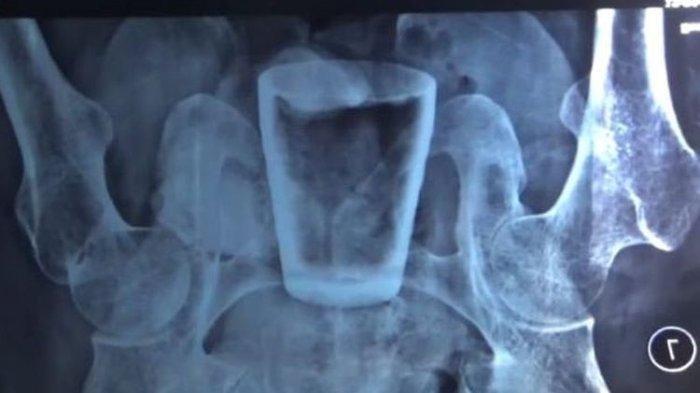

Hasil foto rotgen tubuh warga Jember yang berisi gelas pecah.

Usai dilakukan foto rontgen, ternyata ada gelas kaca di tubuh Lasiadi.

"Iya memang ditemukan gelas dari hasil pemeriksaan rontgen. Gelas di bagian rektum," kata Humas RSUD Balung, dr Doddy Radhi Sakti, Rabu (6/4/2022), mengutip Tribun Jatim.

Dokter mengatakan, gelas tersebut dalam kondisi cuwil atau sedikit pecah. Akan tetapi, pecahan gelasnya tak ditemukan di dalam rektum.

Meski Lasiadi tak mengaku dari mana masuknya gelas tersebut, namun dokter menduga gelas titu dimasukkan melalui anus.

“Kalau dari kami, (gelas itu) memang dimasukkan melalui anus,” kata dr Doddy, Rabu (6/4/2022), mengutip Kompas.com.